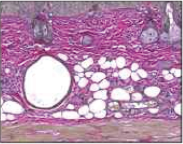

对于皮肤皱纹模型SKH1鼠注入ReGENIN®填充物12周后,评价改善皱纹效果的结果,与其他公司HA填充物(44.73%)相比,ReGENIN®填充物注入组(55.49%)可确认优秀的改善皱纹效果